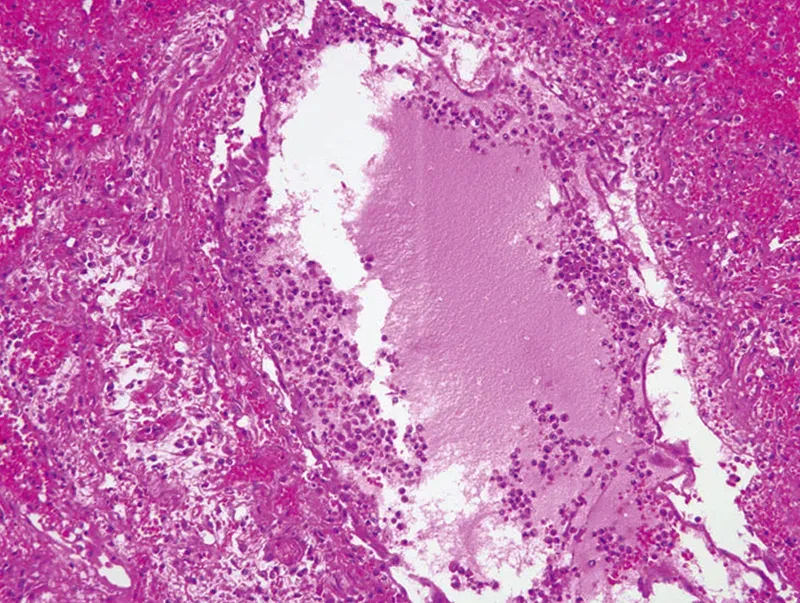

The cytokine-summoned first-responder cells are aggressive and indiscriminate in their destruction. Flooding into the tissues on the wash of leaked interstitial fluids, they use powerful enzymatic and oxidative processes to demolish both friend and foe alike (Image 3). Other cells, such as fibroblasts, simultaneously try to repair this ongoing damage, but when the cytokine-induced destruction continues, the resulting excess collagen makes tissues denser and more fibrous, further inhibiting normal perfusion and drainage.4

In musculoskeletal tissues, the plasma leakage of acute inflammation causes its characteristic swelling and redness. In lung tissue, this fluid buildup causes coughing; and if excessive or prolonged, can lead to breathing difficulties and pneumonia. What's more, capillaries damaged by the inflammatory riot can let the cytokine-rich fluids spill over into the bloodstream, resulting in systemic inflammation and multi-organ failure.5